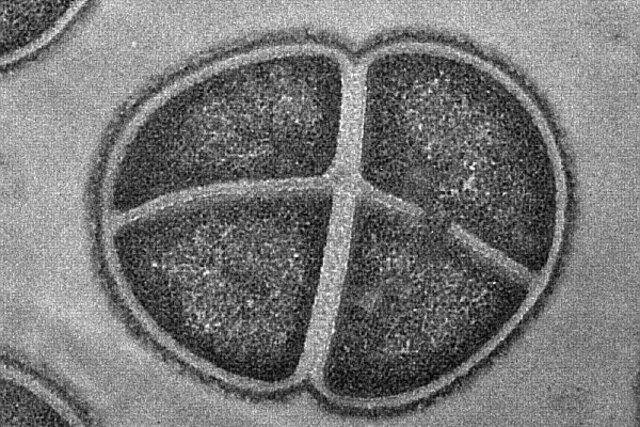

• Биологический жесткий диск, Япония

Биологический жесткий диск, Япония

Biostorage — очень юное направление исследований. Одно из самых серьёзных достижений в этой области было сделано в 2007 году, когда сотрудники Университета Кейо (Япония) успешно закодировали знаменитое уравнение Эйнштейна (E=mc²) в ДНК обычной почвенной бактерии. Поскольку микроорганизмы постоянно воспроизводятся, они могут хранить эту информацию тысячи лет. Перспективы затмевают любую фантазию: один грамм бактерий способен хранить столько же данных, сколько 450 жёстких дисков объёмом 2 Тб!